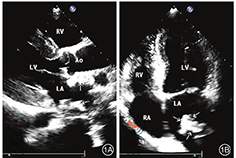

患者,女性,27岁。2010年3月26日因贫血4个月,颜面、下肢浮肿1周到南京医科大学附属无锡第二人民医院就诊。为求进一步诊治入院。实验室检查:血红蛋白(hemoglobin,Hb)57 g/L,血肌酐1657.0 umol/L,血压160/120 mmHg,尿常规蛋白4+,免疫功能正常,抗核抗体谱阴性。超声提示双肾萎缩。考虑慢性肾小球肾炎引起肾功能衰竭。入院诊断为:慢性肾衰竭尿毒症期;慢性肾小球肾炎;肾性贫血;肾性高血压。患者血肌酐高达1657.0 umol/L,入院后立即行右颈内静脉深静脉置管血液透析,硝苯地平控释片和美托洛尔控制血压,叶酸片、速力菲、促红素改善贫血,还原型谷胱甘肽和阿魏酸钠保肾治疗。甲状旁腺激素(parathyroid hormone,PTH)350 pg/ml,α-骨化醇纠正甲状旁腺功能亢进。血液透析后血肌酐降至775 umol/L,继续一周3次血液透析。出院复查Hb 87 g/L,血肌酐215.0 umol/L,血压120/86 mmHg。2010年5月1日因颈静脉置管感染,改行腹膜透析治疗,一天4次。2011年1月2日患者腹膜透析时不慎被他人扯拉腹透管,致皮下卡夫外漏,出现继发性腹膜炎。为避免再次发生腹膜炎,左前臂动静脉内瘘手术进行血液透析治疗。术后内瘘闭塞,继续维持腹膜透析。2015年4月9日腹膜透析管更换术。至此以后一直维持性腹膜透析治疗。期间出现两次腹膜炎,均经抗感染治疗后好转。2018年11月22日因胸闷入院。患者慢性肾病面容,贫血貌。食欲不佳,偶有恶心、呕吐、头晕。目前透析方案为2.5%透析液(每1000 ml含葡萄糖2.5 g、氯化钠5.67 g、氯化钙0.257 g、氯化镁0.152 g、乳酸钠5 g)2000 ml,每天4袋,夜间留腹。24 h超滤700 ml。腹膜平衡试验:总尿素清除指数(KT/V)1.995/周,总肌酐清除率(total creatinine clearance,Ccr)51.966 L/周。实验室检查:血甲状旁腺激素(parathyroid hormone,PTH)1279.00 pg/ml,血钙2.39 mmol/L,血磷2.47 mmol/L,钙磷乘积73.27 mg/dl。心电图检查:正常窦性心律。甲状腺超声显示:甲状腺左右叶后方探及大小分别为0.8 cm×1.3 cm、0.7 cm×1.5 cm低回声结节,边界清,内回声欠均匀,其内可见条状血流信号。考虑甲状旁腺功能亢进,甲状旁腺腺瘤。2018年11月26日经胸超声心动图显示(图1):左心室射血分数为62%,胸骨长轴切面测室间隔舒张末期厚度为1.2 cm,左室后壁舒张末期厚度为1.2 cm,左室舒张末期内径为4.4 cm,左室质量指数(LVMI)141 g/m2,考虑左室壁向心性重构。心尖四腔切面探查二尖瓣血流频谱E/A=0.8 ,二尖瓣环组织多普勒频谱测二尖瓣环外侧e'为7.51 cm/s,二尖瓣环室间隔测e'为6.27 cm/s,E/e'= 12。左心房前后径43 cm。考虑患者舒张功能障碍II级。胸骨旁长轴及心尖四腔心切面见左房内数个不规则增强回声团,不随血流运动。主动脉瓣环及二尖后叶瓣环回声增强,瓣叶活动正常。为明确诊断2018年11月28日行胸、腹部CT平扫检查(图2):左房内团块状钙化,占据左房大部,与超声心动图检查结果一致。患者主动脉弓、双侧乳腺、腹膜、肠系膜、肾动脉同时存在多发性钙化。2019年2月18日在全麻下行甲状腺旁腺次全切除。病理检查示:甲状旁腺腺瘤样增生。术后第2 d复查PTH 23.77 pg/ml,血钙1.32 mmol/L,血磷1.26 mmol/L。患者PTH、血磷恢复正常,存在低钙血症,加强补钙。2019年10月21日患者为行腹膜平衡试验及进一步诊治,收住我院。复查血钙,血磷,PTH均在正常范围。复查超声心动图及胸、腹部CT平扫检查,钙化较2018年11月检查结果无明显改变。

本病例心肌细胞已发生病理性肥大的改变。转移性钙化可发生在全身组织、器官中。钙化累积左心耳、左心房各壁时,形成"椰子样左房"[12]。钙化累积二尖瓣装置,可引起二尖瓣钙化、狭窄[12]。有的患者不得不进行二尖瓣置换术。二尖瓣钙化同时也增加了瓣膜置换术的难度。研究表明当左房内大量钙化时,如果累及心内膜,需要在体外循环下,行心内膜切除术以清除钙化[13]。本病例左房转移性钙化虽未造成二尖瓣明显钙化和狭窄,但已累及左房部分游离壁,并在左房内呈团块状附着,最大约1.1 cm×2.6 cm。可能需要长期随访二尖瓣受累情况及有无狭窄,左房团块状钙化变化,判断是否需要外科手术干预。左房壁钙化可降低左房顺应性,增加左房压。随时间的延长出现左室舒张功能障碍[14]。本病例存在左室舒张功能障碍,一方面因患者肾性高血压所致,另一方面因左房钙化引起左房壁顺应性减低。本病例超声心动图提示左室壁肥厚,LVMI达141 g/m2。研究表明心肌细胞存在FGFR,FGF-23与FGFR结合,可刺激心肌细胞肥大,间质纤维化,使心肌发生向心性重构[15]。

本病例除心脏钙化外,部分血管(主动脉弓、肾动脉)也存在钙化。有研究表明心血管疾病风险与血管钙化有关,血管钙化积分越高,心血管疾病的风险也越高[16]。由此可见,本病例发生心血管疾病风险增加。本病例也存在双侧乳腺钙化,这种钙化大多数都是良性的,可发生于乳腺导管、乳腺血管及乳腺组织中[17]。本病例还合并广泛的腹膜钙化,长期的腹膜透析和反复的腹膜炎是形成腹膜钙化的危险因素[18]。合并腹膜钙化的患者可表现为恶心、呕吐及腹痛。